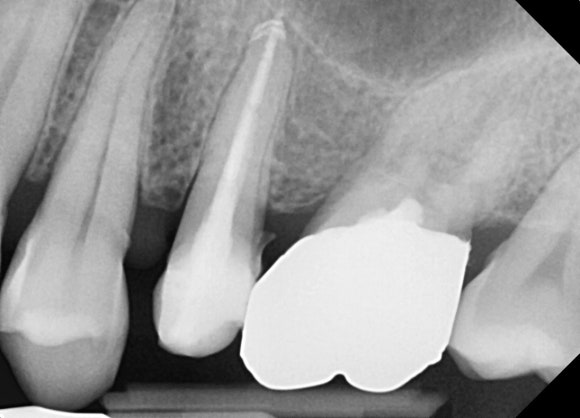

20250318

해당 치아를 신경치료하였습니다.

그리고 뿌리에서부터 머리까지 지지해주는

레진파이버 포스트를 뿌리에 식립해줍니다.

고층 건물의 철골 구조라고 보시면 됩니다.

머리에 얹은 크라운이 이탈하는 확률을 줄여줍니다.

20250325

새로이 만들어진 머리에 크라운을 씌워주면 치료는 종료됩니다.

그리 복잡하거나 어려운 치료가 아닙니다.

내원 횟수도 일반적인 신경치료 케이스와 크게 차이나지 않습니다.